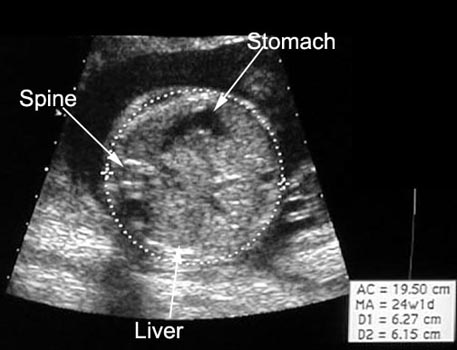

Measurements |